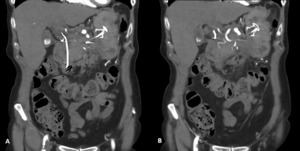

Despite biochemical improvement, the patient’s clinical course was complicated by persistent systemic inflammation and escalating abdominal pain. A contrast-enhanced computed tomography (CT) scan demonstrated features consistent with severe acute necrotizing pancreatitis, including extensive pancreatic oedema, areas of hypo-enhancement, marked peripancreatic fat stranding, and multiple peripancreatic fluid collections. The largest collection measured approximately 10 × 15 × 5 cm (Figure 1).

Ten days following initial presentation, the patient was referred for endoscopic drainage of the peripancreatic fluid collections. Endoscopic ultrasound-guided drainage was performed with insertion of a lumen-apposing metal stent (AXIOS) and an additional plastic stent into the largest collection. A repeat contrast-enhanced CT scan was recommended two weeks following stent placement to assess treatment response (figure 2).

On this interval CT imaging, the distal common hepatic artery (CHA) and the proximal left (LHA) and right hepatic arteries (RHA) were noted to be non-opacified, with soft tissue attenuation tracking along the expected course of these vessels. In the clinical context, these findings were most consistent with arterial thrombosis with associated vessel expansion or pseudoaneurysm formation, giving rise to the observed imaging appearance.